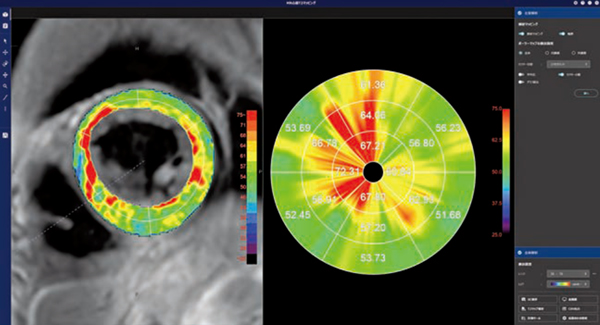

■CT心筋ストレイン解析(W.I.P.)

「CT心筋ストレイン解析」は,2024年に発表した「PhyZio/dynamics2.0」という弊社独自の動態解析技術を用いて開発を行っている。MR心筋ストレイン解析と同様に,4D-CTのデータを開くと,短軸像および長軸像(2ch,3ch,4ch)のすべての断面で左室心筋内壁と外壁の輪郭線を自動抽出してボクセルトラッキングを行い,心筋のストレイン解析を行う(図4)。

MRIは,循環器領域の診断において重要な検査である一方,検査時間の長さや撮像禁忌などの課題もある。CTは,国内においてMRIに比べアクセスが良く,撮影も短時間で行えるため,その実用性の高さからストレイン解析においてもCTの活用が期待される。

図4 CT心筋ストレイン解析(W.I.P.)